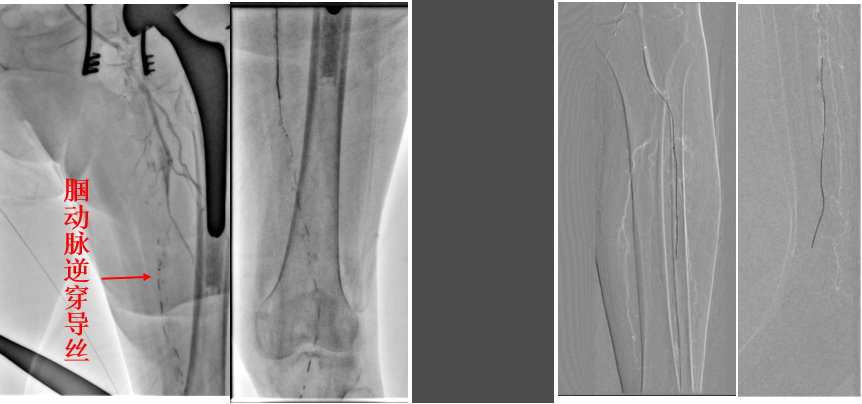

图为:术前造影:腘动脉P3胫前起始部显影

图为:导丝进入ATA,远端无法回真腔

图为:足背动脉穿刺对接

图为:药涂球囊扩张图为:药涂球囊扩张

图为:支架植入

图为:术后造影